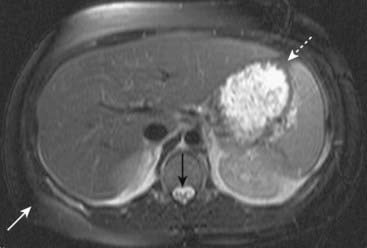

Figure 20-2 Subcapsular hematoma of the kidney.

A, Axial T1-weighted fat-suppressed image demonstrates a bright subcapsular hematoma (solid white arrows) involving the left kidney laterally. We can tell that this is a T1-weighted image because cerebrospinal fluid (CSF) in the spinal canal is dark (open white arrow). B, Axial T2-weighted, fat-suppressed image again demonstrates a slightly bright left subcapsular hematoma with a dark rim of hemosiderin (dotted white arrows) indicating surrounding older blood. There is a small amount of adjacent left perinephric fluid (solid white arrow). The bright signal of the CSF helps us to recognize this image as a T2-weighted image (open white arrow).